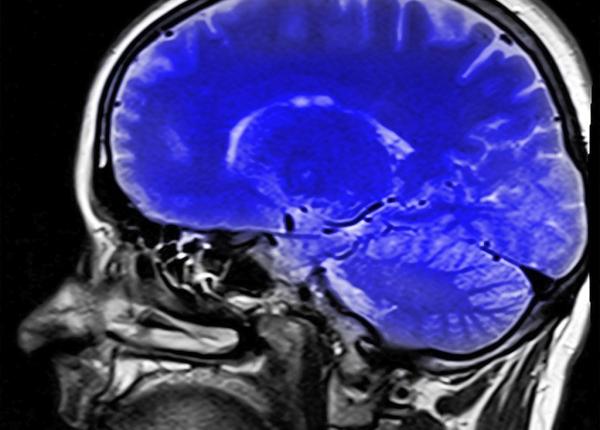

Ce se întâmplă în creier când folosești excesiv smartphone-ul

Cercetătorii susțin că folosirea constantă a smartphone-ului ar afecta creierul asemeni drogurilor.

Dieta ieftină, probleme pentru creier. Ce să nu faci

Consumarea unei diete de tip fast food timp de cel puțin o săptămână poate afecta subtil funcția creierului și ar încuraja tinerii să mănânce excesiv.